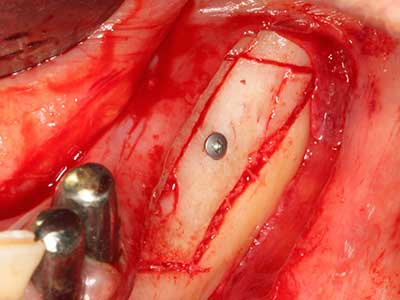

As shown in the past, basically any bone surgery procedure represents a possible indication for piezo surgery. Thus preparation of the mobile segment in distraction osteogenesis (Fig. 23-25) and sandwich osteotomy uses special attachments without endangering the blood supply to the crestal section, which is essential for the success of both techniques (Gonzalez-Garcia, Diniz-Freitas et al. 2008).

Purely orthodontic indications include orthognathic surgery, genioplasty (Fig. 27-30) and orbital decompression in patients with advanced endocrine orbitopathy as a result of Basedow’s disease (Ponto, Zwiener et al. 2014). Piezo devices are also used in maxillofacial surgery and to remove tumours at the base of the skull in various hospitals.